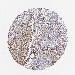

UROTHELIAL CANCER - Protein expressioni

A mouse-over function shows sample information and annotation data. Click on an image to view it in a full screen mode. Samples can be filtered based on level of antibody staining by selecting one or several of the following categories: high, medium, low and not detected. The assay and annotation is described here.

Note that samples used for immunohistochemistry by the Human Protein Atlas do not correspond to samples in the TCGA dataset.

Antibody stainingi

Antibody staining in the annotated cell types in the current human tissue is reported as not detected, low, medium, or high, based on conventional immunohistochemistry profiling in selected tissues. This score is based on the combination of the staining intensity and fraction of stained cells.

Each image is clickable and will lead to virtual microscopy that enables deeper exploration of all samples and also displays staining intensity scores, fraction scores and subcellular localization as well as patient and tissue information for each sample.

Antibody HPA001824

Staining

High

Medium

Low

Not detected

Intensity

Strong

Moderate

Weak

Negative

Quantity

>75%

75%-25%

<25%

None

Location

Nuclear

Cytoplasmic/membranous

Cytoplasmic/membranous,nuclear

Urothelial carcinoma, High grade

Urothelial carcinoma, Low grade

Adenocarcinoma, NOS